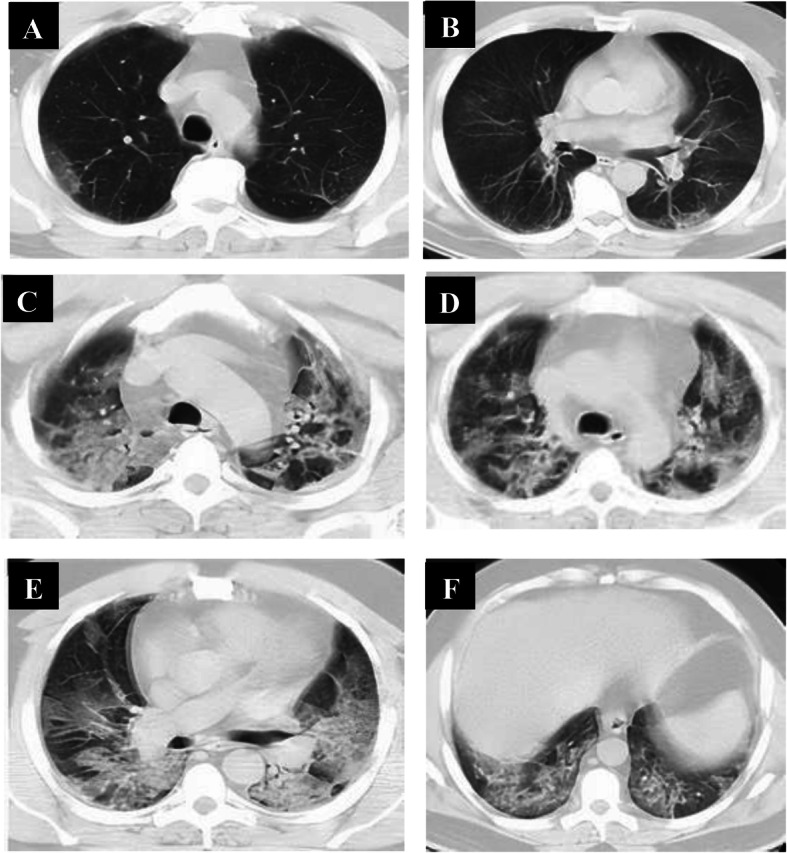

Follow-up chest CT studies were done for patients in the early phase (n = 60) after 4–5 days from onset of symptoms, and we reported no CT lung abnormalities in 8 patients and positive CT findings in 52 patients. CT lung abnormalities were progressed than the initial CT: GGO only in 7 patients, consolidation only in 8 patients, combined GGO and consolidation in 38 patients, and crazy-paving in 4 patients. Peripheral distribution was noted in 8 patients and diffuse distribution in 44 patients. 52 patients had bilateral affection with two lobes of affection in 12 patients, three lobes of affection in 19 patients, 4 lobes of affection in 15 patients, and 5 lobes of affection in 6 patients. Total lung severity score: 8 patients with score 10, 4 patients with score 13, 25 patients with score 16, and 15 patients with score 17 (mean of 13.11 ± 5.657) (Figs. 4, 5, and 6).

Fig. 4.

A 33-year-old male patient complaining of fever, sore throat, and cough (mild symptoms). Non-contrast axial chest CT (a, b) 2 days after onset of symptoms (early phase) revealed two patchy areas of consolidation seen at the right lung middle and lower lobes with air bronchogram and left-sided pleural effusion. With the persistence of the same symptoms (no respiratory distress), follow-up chest CT (c–f) 7 days from the onset of symptoms revealed more extensive lesions in the form of multiple confluent patchy areas of ground-glass opacities, consolidation, and crazy-paving seen scattered at both lungs: central and peripheral in distribution and bilateral minimal pleural effusion

Fig. 5.

A 36-year-old female patient complaining of dyspnea, fatigue, fever, and cough (severe symptoms). Non-contrast axial chest CT (a, b) 1 day from the onset of symptoms (early phase) revealed normal CT study. With the persistence of the same symptoms, follow-up chest CT (c–f) 6 days from onset of symptoms revealed multiple extensive confluent patchy areas of ground-glass opacities and consolidation seen scattered at both lungs: central and peripheral in distribution

Fig. 6.

A 42-year-old female patient complaining of diarrhea and cough (mild symptoms). Non-contrast axial chest CT (a, b) 2 days from onset of symptoms (early phase) revealed few patchy areas of ground-glass opacities and consolidation seen at basal segments of both lungs lower lobes: peripheral in distribution. With the progression of symptoms (developed dyspnea), follow-up chest CT (c–f) 6 days from onset of symptoms revealed more extensive lesions in form of multiple confluent patchy areas of ground-glass opacities, consolidation, and crazy-paving seen scattered at both lungs: central and peripheral in distribution